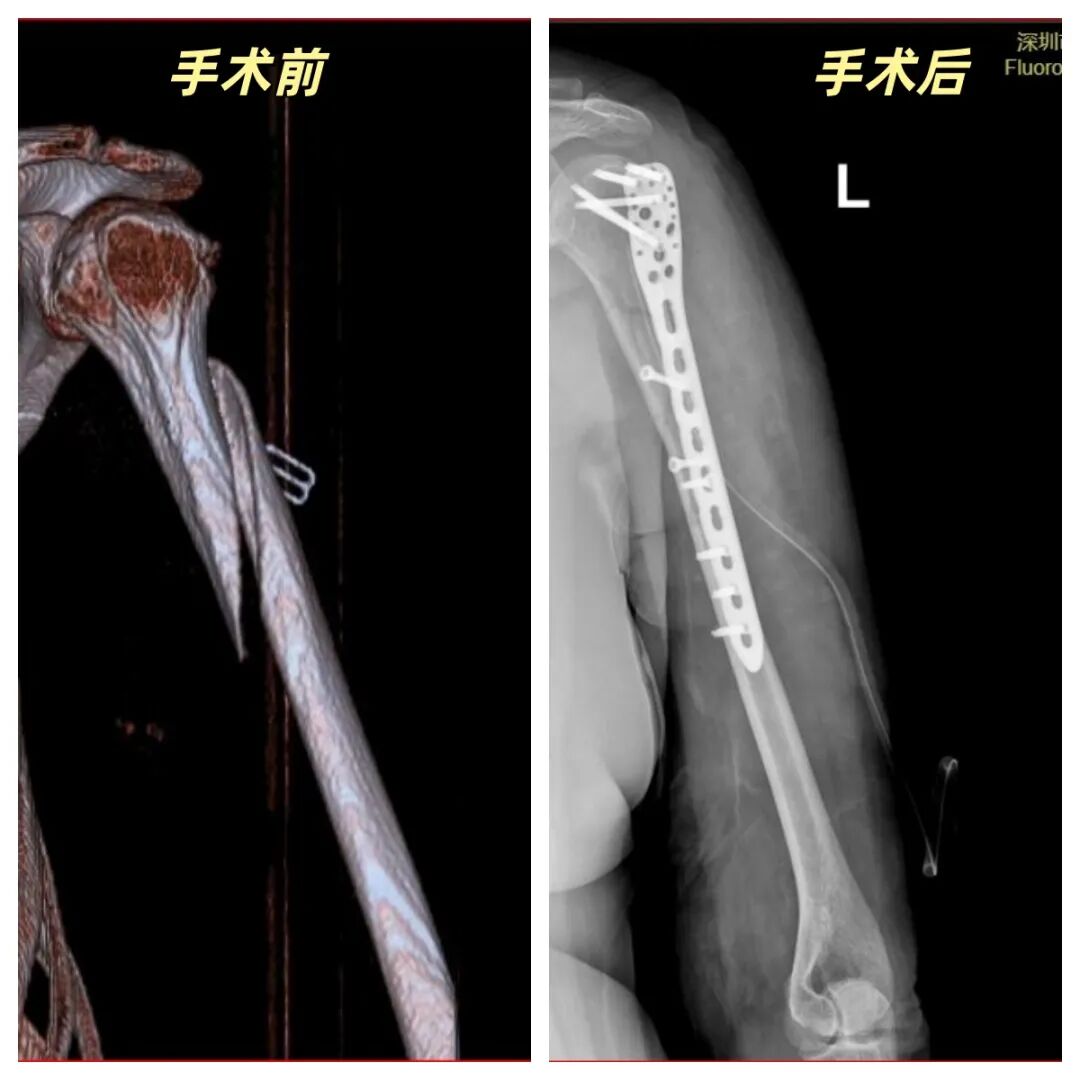

在当地医院,X光片显示为复杂的肱骨近端长螺旋形粉碎性骨折。这种骨折形态特殊,复位与固定的难度远超普通骨折。对于一位身处异国、语言不通的人来说,后续治疗的复杂性更增添了巨大的焦虑。

手术前,骨科组织专家进行了充分的术前讨论,为患者制作了周密的手术方案。手术中,在南方医院专家的协助下,戴冠东教授团队凭借精湛的技艺,精巧地将螺旋分离的骨折块解剖复位,完美地解决了长螺旋骨折的固定难题。整个过程展现了团队高超的技术水准与无缝的协作能力。